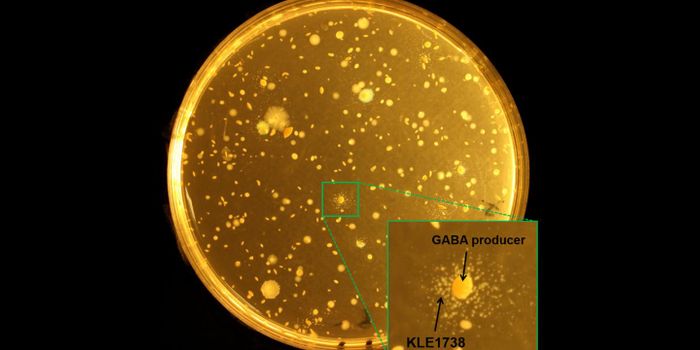

FEB 18, 2019MicrobiologyScientists are learning more about how specific strains of bacteria in our guts are connected to various aspects of our ...

AUG 08, 2018MicrobiologyGut bacteria can have a powerful effect on brain function.